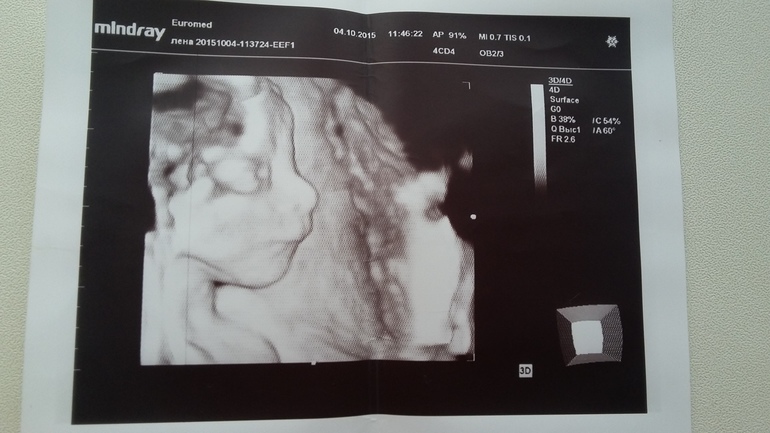

вчера не было возможности отчитаться, висела на телефоне,а с него вообще не удобно писать) В общем у нас все хорошо)))поставили срок по узи 21+1, развиваемся по сроку, ходили на 3Д, девочки это такая радость когда видишь своего малыша)))))и у нас курносенькая, носастенькая ДОЧЕНЬКА)))))!!!!!!!!!!

Мужа конечно сразу настраивала что будет доча у нас, но он все таки думал что пацан)ну ничего,самое главное что у нас все хорошо и прекрасно) Весим 420 гр.это все что я запомнила)))теперь у нас официально вторая доченька чему я не сказано рада)))))ну и фото моей сладкой булочки

так четко видно, классно прям!!! тоже надо такое себе сделать)) Поздравляю с радостной новостью)))Что же быть приятней такой вот красоты))